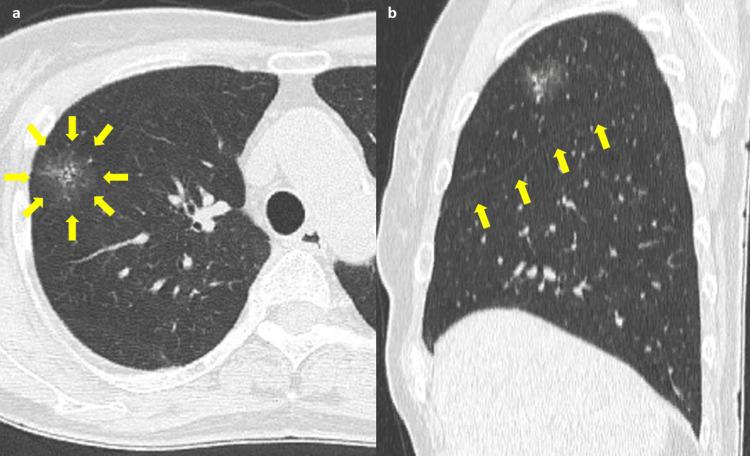

针对一名存在不完全性水平裂及右上肺静脉多处异常的患者行整块右上叶双肺段切除术

Variations in the anomaly of the right superior pulmonary vein can lead to perioperative complications if misunderstood. Additionally, incomplete fissures increase the complexity of performing pulmonary anatomical resection. Therefore, accurate preoperative anatomical assessment using three-dimensional computed tomography is crucial for ensuring safe surgery. We herein report a case of en bloc right upper bilobectomy via uniportal video-assisted thoracic surgery in a patient with an incomplete minor fissure and a complex anomaly of the right superior pulmonary vein.

右上肺静脉异常的变异如果被误解,可能导致围手术期并发症。此外,不完全裂增加了进行肺解剖性切除的复杂性。因此,使用三维计算机断层扫描进行准确的术前解剖评估对于确保手术安全至关重要。我们在此报告一例通过单孔电视辅助胸腔镜手术对一名存在不完全小裂和右上肺静脉复杂异常的患者进行整块右上叶双肺叶切除术的病例。